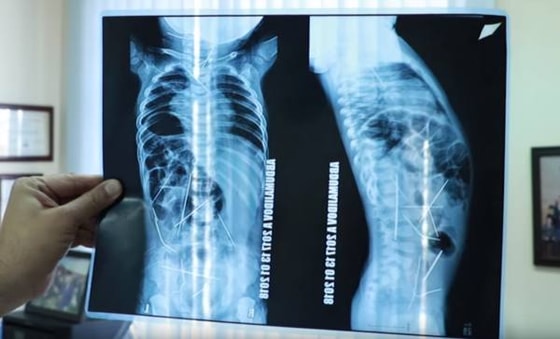

Новые подробности в истории мальчика из Ферганы с 16 иголками в теле

В январе общественность Узбекистана взбудоражила история об 11-месячном Азизбеке, которого доставили в Ташкент для проведения сложнейшей операции по извлечению из тела 16 иголок. Сложные хирургические операции помогли избавиться от инородных предметов, а мальчик вскоре пошел на поправку и был выписан из больницы.

Как стало известно, все должные экспертизы и обследования были проведены. В результате выяснилось, что иголки в теле младенца оказались не под внешним воздействием. Проведенная экспертиза в отношении близких ребенка также показала, что они вменяемы. Иголки оказались в теле мальчика оральным путем, но из-за перистальтики пищевода и сокращения мышц "мигрировали" в разные части организма.

Оказалось, что бабушка ребенка занимается пошивом тюбетеек на дому. До того, как внука госпитализировали, она приобрела упаковку иголок, которые позже исчезли. Вероятно, что мальчик проглотил целую пачку иголок, которые рассеялись по организму, цитирует заявление прокуратуры области ресурс UZ24.uz.